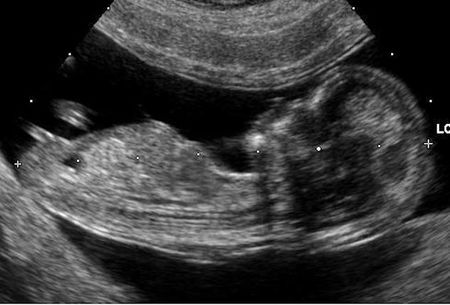

La donna, che di mestiere fa la bracciante agricola, aveva partorito il suo ultimo figlio nel 2005. Un maschietto sano, nato con il parto cesareo. Lui e la mamma, allora 37enne, stanno bene e tornano a casa. Ma da quel giorno la donna ha continuamente avvertito forti dolori all’addome. Nonostante le numerose visite in diverse cliniche, nessun medico è riuscito ad individuare la fonte di tanto dolore. Così, per 13 anni, la donna ha cercato di rimediare come poteva: antidolorifici, ore di riposo, accorgimenti. Ma la situazione invece che migliorare continua a peggiorare, sotto gli occhi del marito e degli altri 4 figli. Fino a quando la situazione precipita il 7 gennaio. Viene ricoverata d’urgenza e subisce ben 5 trasfusioni. Esausta la donna si è rivolta ai medici dell’Ospedale di Padova che, finalmente, sono riusciti a scoprire il motivo di tanto malessere: la donna portava ancora in grembo un feto gemello dell’ultimo nato. L’altro feto si era sviluppato in una diversa placenta rispetto al gemello, e dopo il parto era scivolato nella parte destra dell’addome, rimanendo invisibile per 13 anni alle tante ecografie fatte negli anni. I medici hanno detto alla pugliese che si sarebbe trattato di una femminuccia. Ora la donna sta valutando di presentare un esposto.

(Credits immagine di copertina: commons.wikimedia, X.Compagnion )